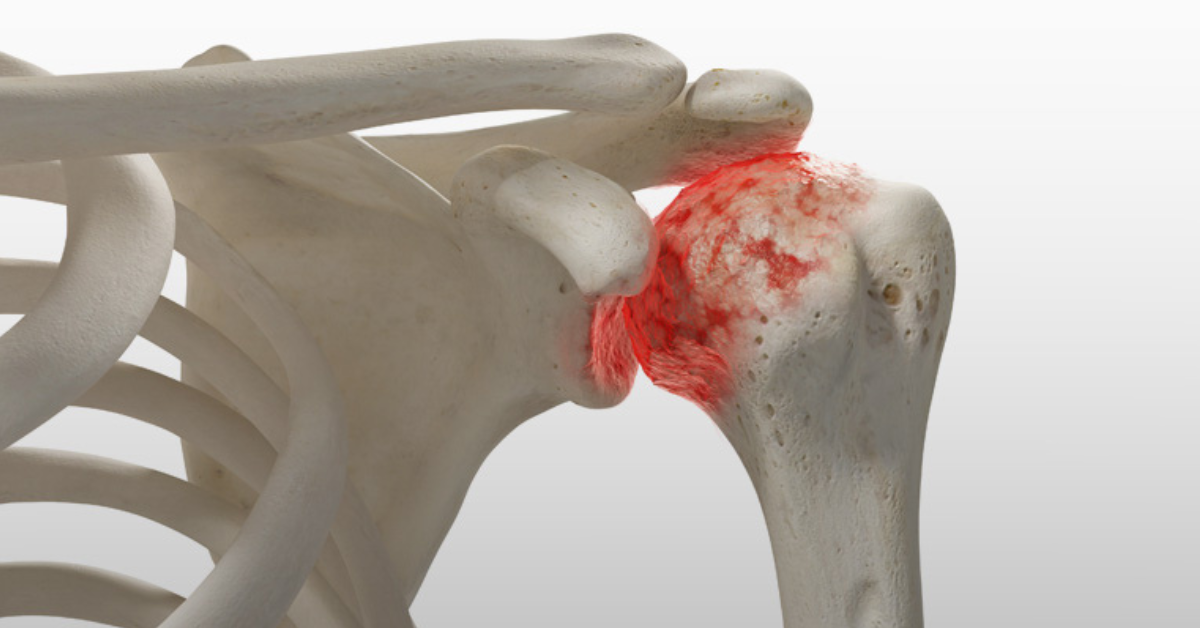

Osteoarthritis Of The Shoulder Joint RoyaltyFree Stock Photo Shoulder Surgery Osteoarthritis Shoulder replacement is a major surgery that requires a long recovery and rehabilitation process. Shoulder replacement surgery is typically reserved for advanced arthritis of the shoulder joint, but can also be used for complex fractures and other problems that cannot be. Shoulder arthroscopy is a minimally invasive surgery to treat shoulder problems, including shoulder impingement and rotator cuff. Surgery is. Shoulder Surgery Osteoarthritis.

Shoulder Arthritis Signs, Symptoms & Surgery Colorado Sports Doctor Shoulder Surgery Osteoarthritis Shoulder arthroscopy is a minimally invasive surgery to treat shoulder problems, including shoulder impingement and rotator cuff. If your shoulder osteoarthritis pain becomes severe and you lose significant use of your shoulder, a doctor may recommend surgical treatment. Shoulder replacement surgery is typically reserved for advanced arthritis of the shoulder joint, but can also be used for complex fractures and. Shoulder Surgery Osteoarthritis.

Shoulder Pain 3D Sports Medicine & Orthopaedic Center Shoulder Surgery Osteoarthritis Physical therapy is necessary to. Conditions that can damage the joint include:. Shoulder replacement surgery is done to relieve pain and other symptoms that result from damage to the shoulder joint. Surgery is an invasive treatment option for people with osteoarthritis (oa) where a joint (usually the hip or knee) problem is addressed to increase. Shoulder replacement surgery is typically. Shoulder Surgery Osteoarthritis.